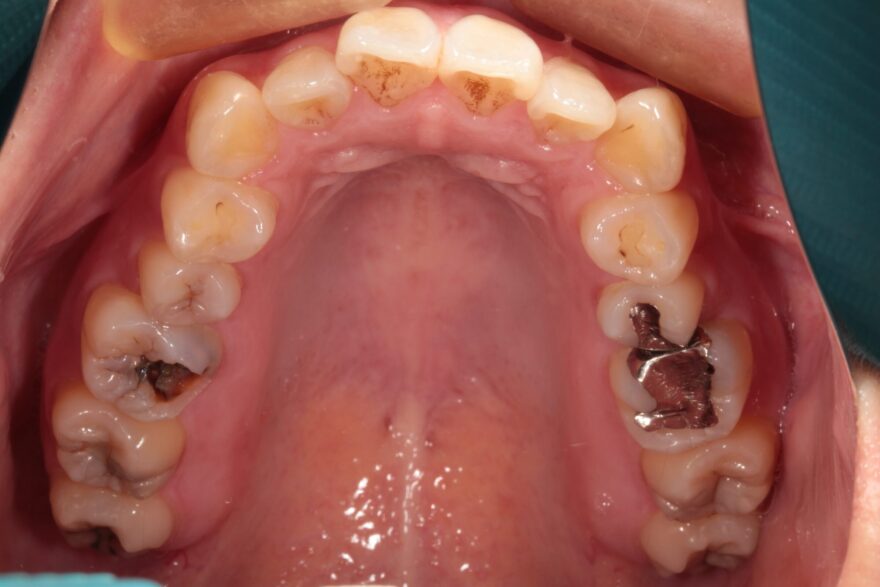

ガタガタに重なっている部分や、過去の治療で銀歯も入っています。

昔から歯は弱いほうで、トラブル続きだったこともあり、色々治療はしていましたが根本解決はせず…

当院の院長によるセラミック治療と矯正専門医の芝田Dr.によるワンストップ治療で一生困らないように治療していこうと踏み切ることが出来ました。